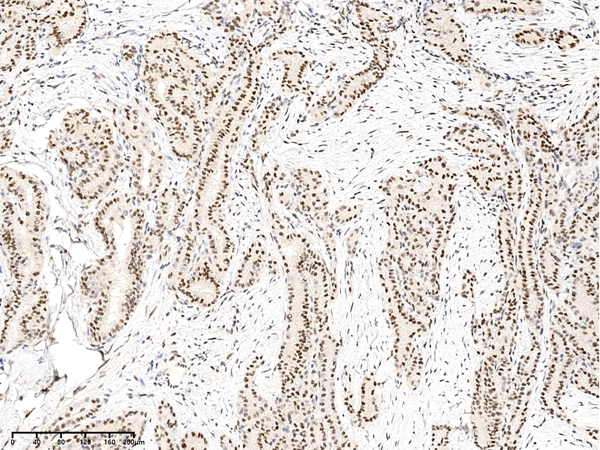

IHC (Immunohistochemistry)

(Immunochemical staining of human Phospho-CREB (Ser133) in human thyroid cancer with rabbit polyclonal antibody at 1:100 dilution, formalin-fixed paraffin embedded sections.)